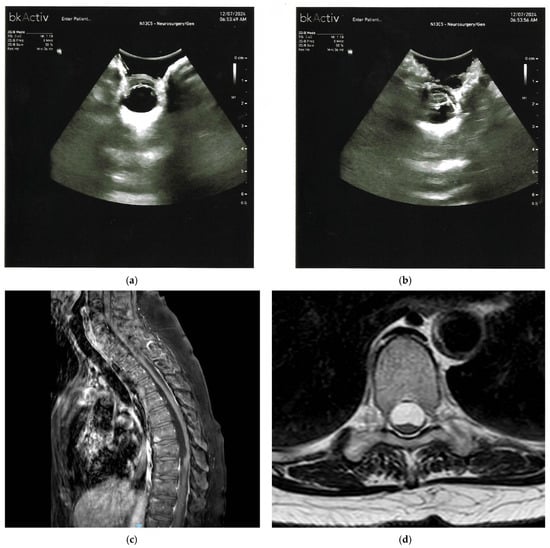

| Spinal Chronic Subdural Hematoma (CSSDH) | Hyperintense on T1 or T2 (late subacute); isointense or hypointense (chronic); elongated dorsal collection with cord displacement. | Hypoechoic or anechoic subdural collection beneath echogenic dura; internal echoes or septations; bounded by echogenic membrane. |